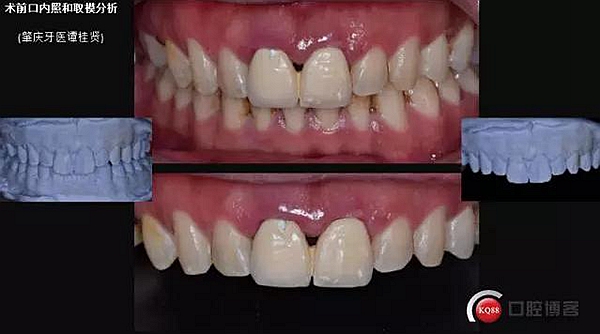

患者:32歲 男 要求重新修復前牙

主訴:上前牙咀嚼無力牙齦易出血,近日來烤瓷冠松動脫落。

現(xiàn)病史:#11#21金屬烤瓷冠修復近十年了,近年來慢慢出現(xiàn)食物嵌塞不密貼,也非常影響美觀,但提起看牙醫(yī)便會驚出一身冷汗,近幾個月來牙冠慢慢出現(xiàn)松動,出現(xiàn)咬合痛,緊張的走進了門診。

口內(nèi)檢查:很輕易就取下牙冠,均為殘冠殘根且繼發(fā)齲,#21尤為嚴重,已到齦下,牙周探診1.5mm,X線檢查:根尖陰影,欠充。

診斷:#11#21殘根,繼發(fā)齲,輕度牙周炎。

一診口內(nèi)照

口外照